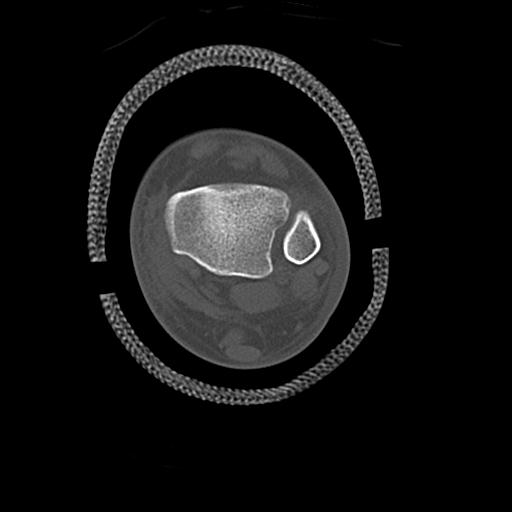

56476 8/28 4R 1/21 2R 左足関節 デジカメ写真 72歳女性 右足関節AS